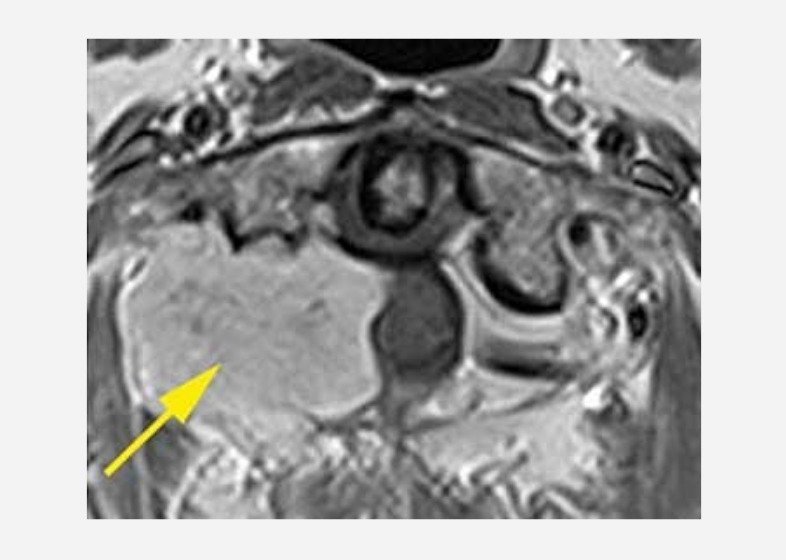

硬膜内髄外腫瘍(神経鞘腫)

56歳女性

第1-2頚椎部に腫瘍を認める

硬膜内髄外腫瘍(神経鞘腫)56歳女性

腫瘍によって脊髄は強く圧迫されている